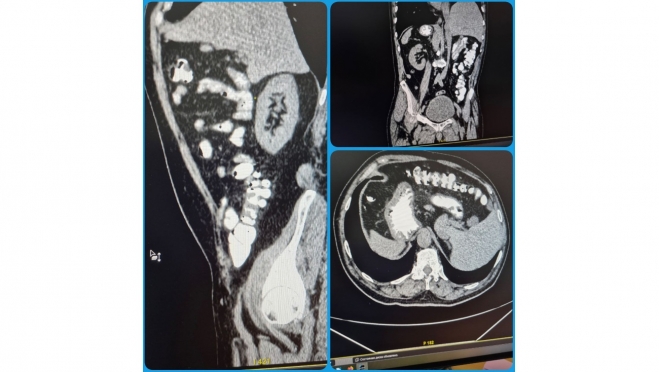

При проведении КТ-обследования брюшной полости пациента врачи Балаковской городской больницы увидели не совсем обычную картину, сообщает телеканал «Саратов 24». Оказалось, что у мужчины все органы располагаются зеркально: печень — слева, сердце — справа, имеется зеркальное отображение аорты и легких.

Подобная анатомическая аномалия называется транспозиция органов и встречается крайне редко.